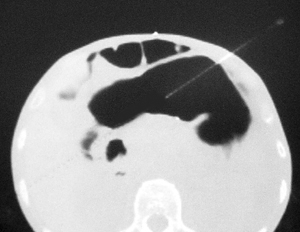

Step 7: Confirm that the needle tip is in the gastric lumen using axial CT sections (use lung windows). It is critical to ensure that the needle is in the lumen and not merely tenting the surface. Introduce the spring coil end of the 0.035 inch diameter guidewire into the needle while maintaining slight tension on the trailing gastrointestinal anchor thread. Using the guidewire, push the gastric anchor out of the needle into the gastric lumen. Maintenance of slight tension on the trailing thread prevents jamming of the thread within the lumen of the needle.

Confirm needle tip location using lung windows |